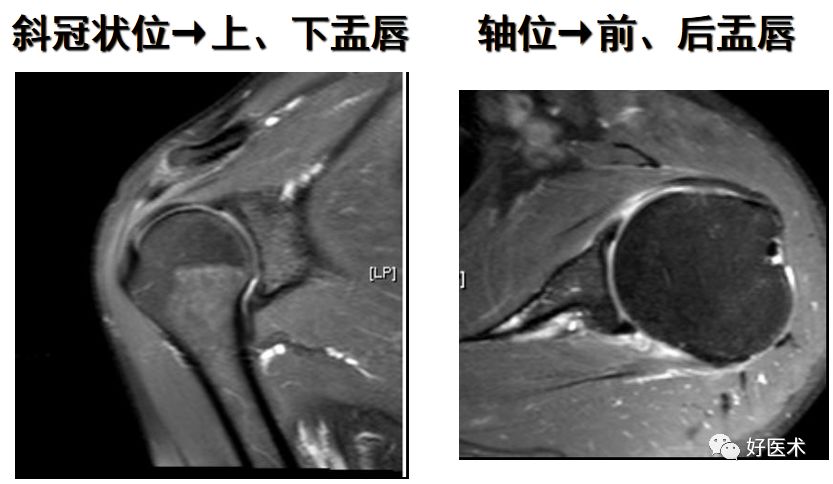

正常盂唇的MR表现

正常关节盂唇可表现为多种形态,其中三角形多见,其次可表现为钝圆形、扁平盂唇等。前盂唇往往较后盂唇锐利

正常盂唇